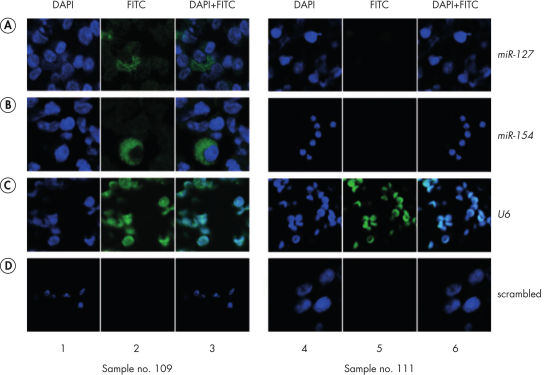

結果検証のためのコントロールプローブ

miRCURY LNA miRNA Detection Control Probesは、ISHやノーザンブロッティング用のmiRCURY LNA Detection Probesとともに使用するように設計されています。 コントロールプローブは長さおよびLNA設計が検出プローブと類似しており、同じTm 範囲内で設計されています。 U6 snRNA陽性コントロールとスクランブル陰性コントロールは、ISH実験の最適化およびトラブルシューティング中に使用することができますので、これらのコントロールで実験結果を検証ができます( Detection of hsa-miR-127 and hsa-miR-154参照)。

Detection of hsa-miR-127 and hsa-miR-154 by fluorescent in situ hybridization using miRCURY LNA detection probes in cryopreserved bone marrow cells from an acute myeloid leukemia patient.

Detection of hsa-miR-127 and hsa-miR-154 by fluorescent in situ hybridization using miRCURY LNA detection probes in cryopreserved bone marrow cells from an acute myeloid leukemia patient.